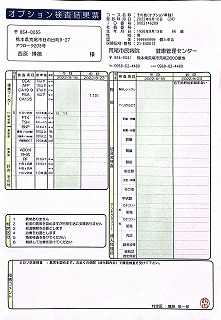

090 脳ドック

2024.18.14 荒尾市民病院 2023.08.10 荒尾市民病院

2024 PDF 2023 PDF

22.9.16 荒尾市民病院